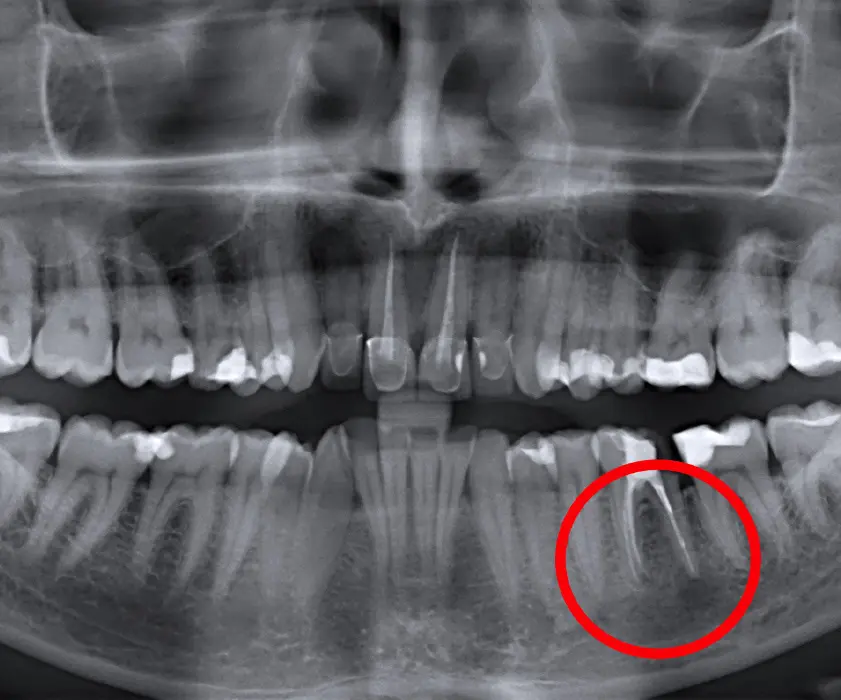

Cistektomija je poseg oralne kirurgije, ki odstranjuje periapikalne lezije zob, oz. abscesov, granulomov in različnih cist. Zgoraj omenjene tvorbe, oz. spremembe, so vidne okoli korenine zoba in se najbolj pogosto opazijo na panoramski sliki, oz. ortopanu, ko bolnik pride k zobozdravniku zaradi hude bolečine in otekline.